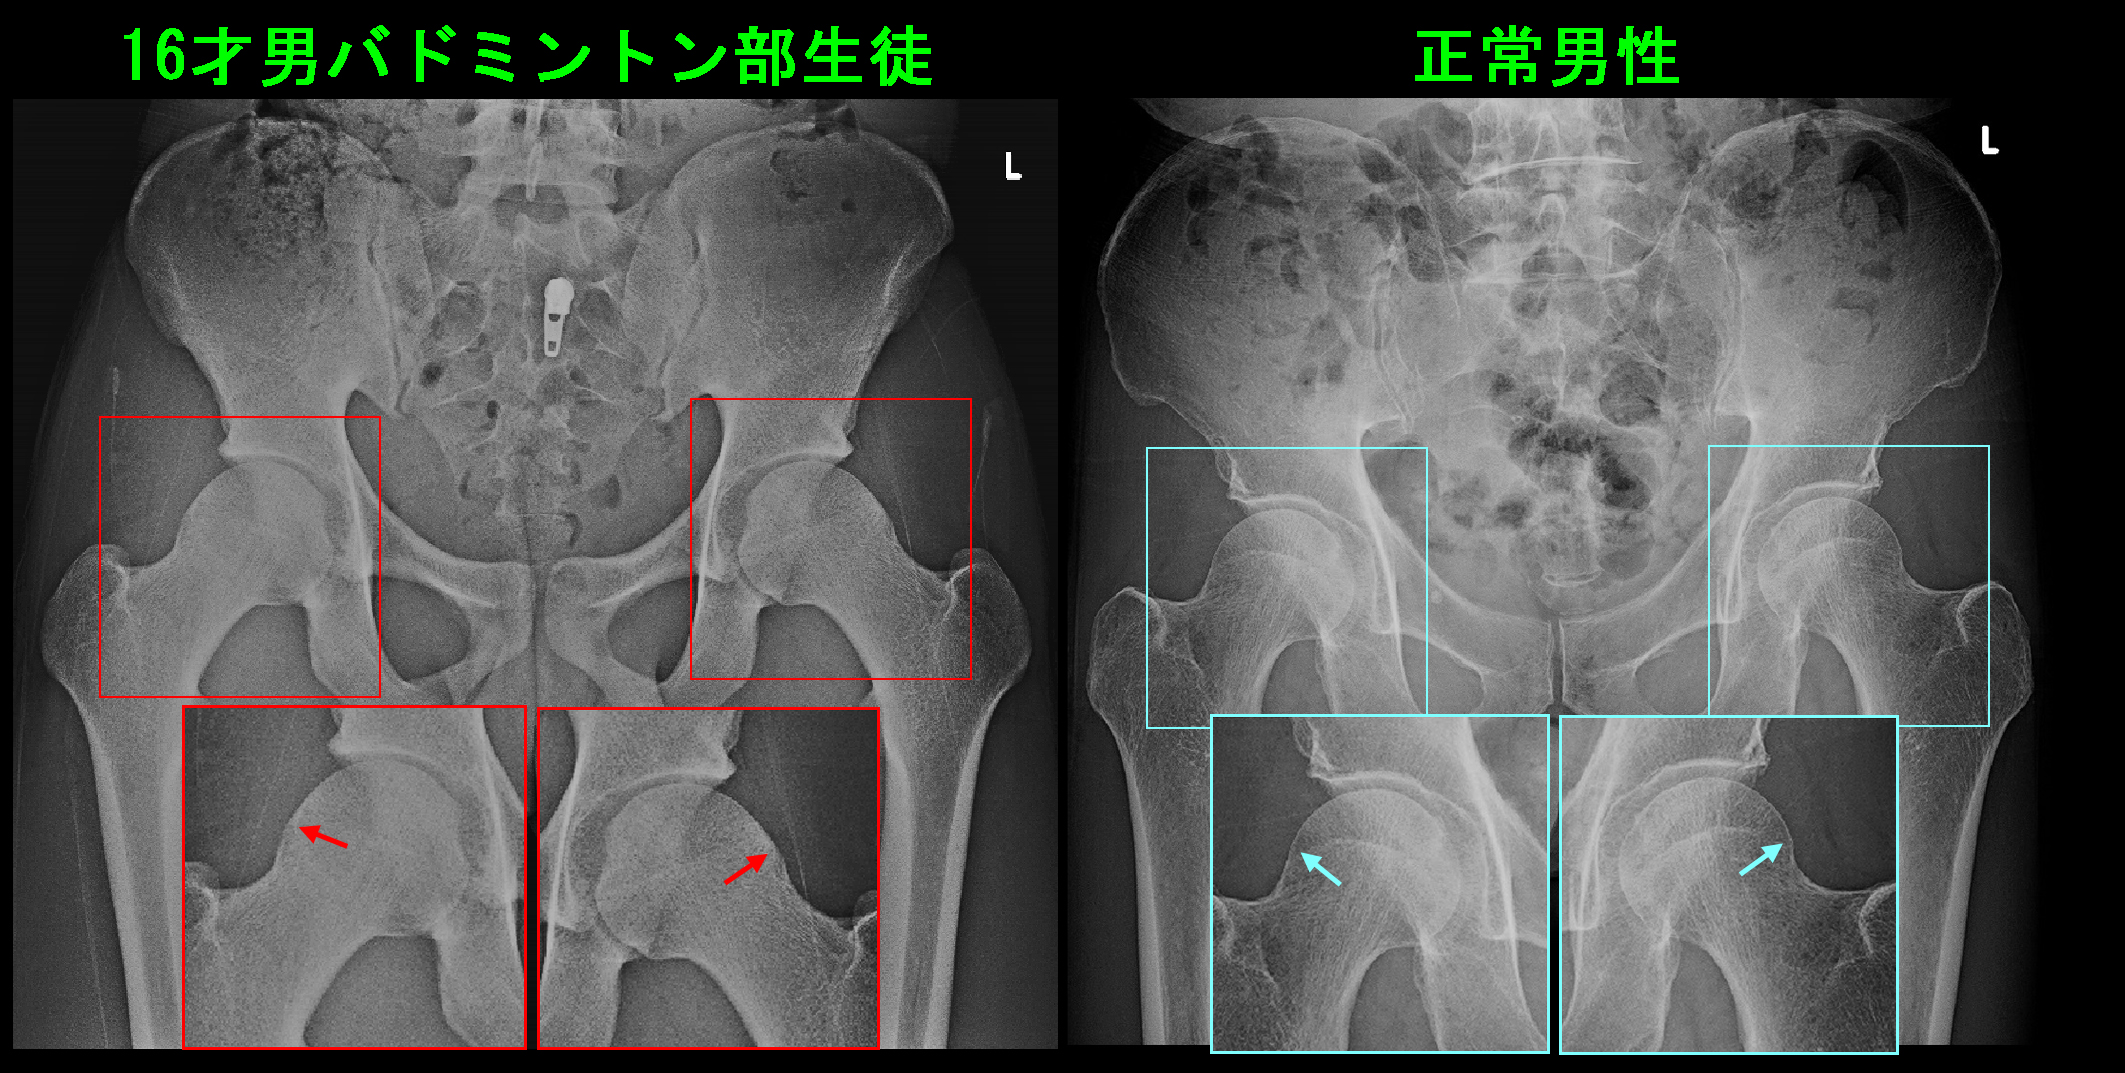

S君の股関節レ線像と正常男性の股関節レ線像を比較すると、微妙ですが大腿骨頭部の外側部分が少し盛り上がっています。これがFAIの原因となります。大腿骨骨頭の外側部が盛り上がっていると、股関節を屈曲していった時にその膨隆部が臼蓋の周囲の関節唇を圧迫して損傷することになるのです。